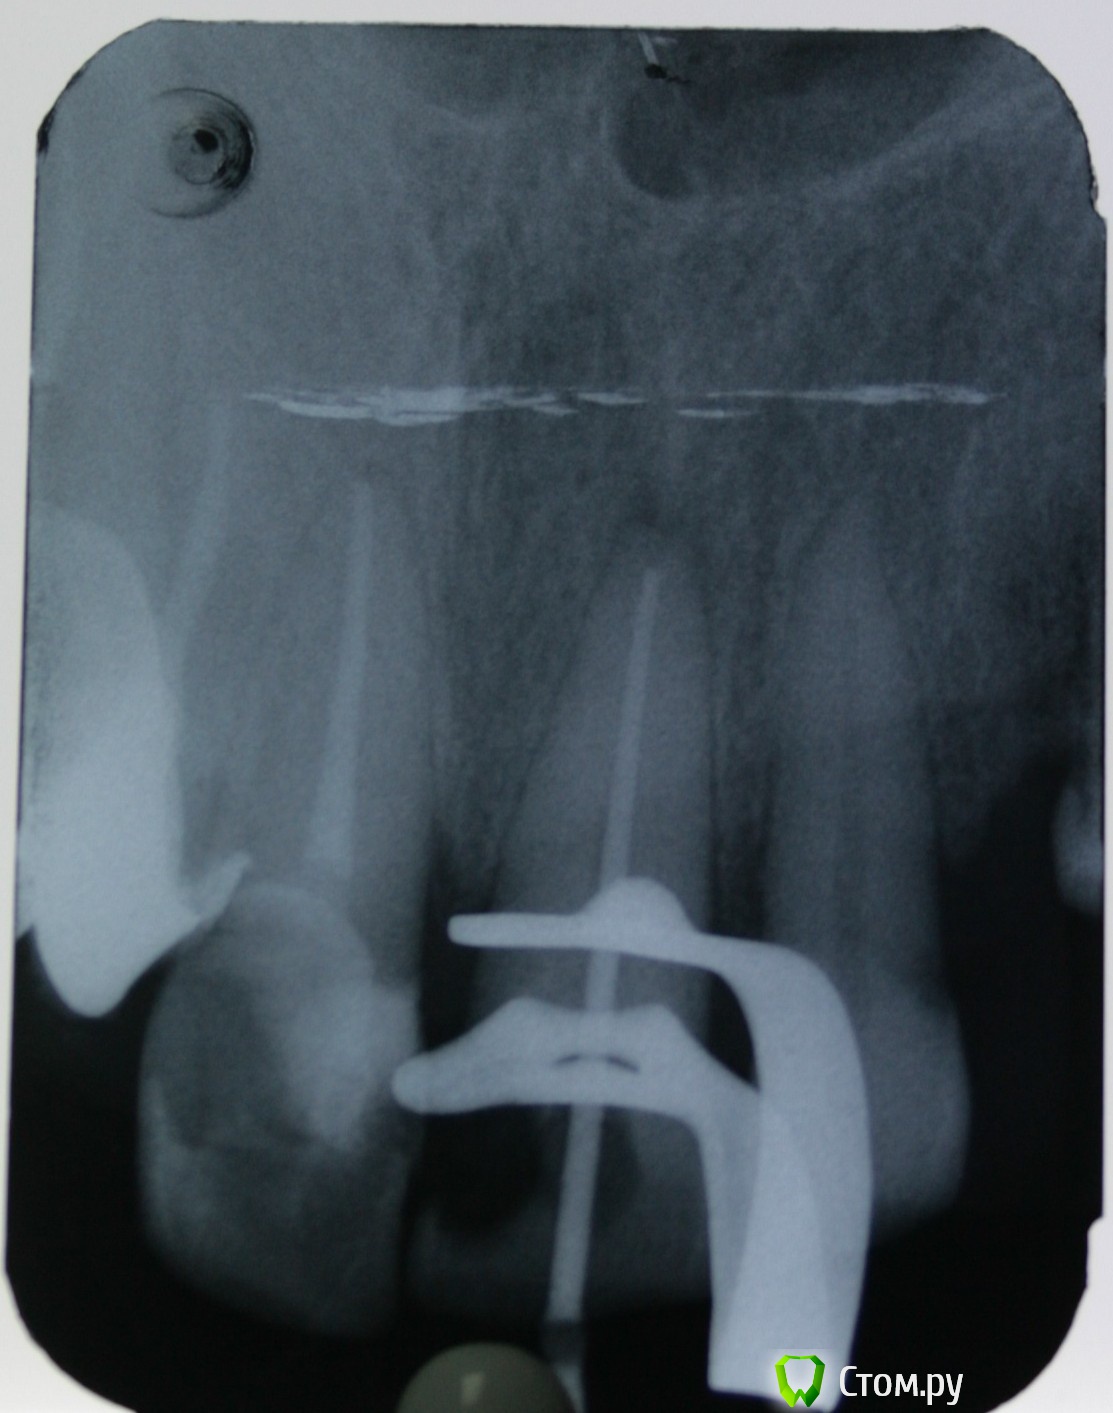

St. Опубликовано 7 ноября, 2014 Автор Поделиться Опубликовано 7 ноября, 2014 Покритикуйте, кому не лень ! Пациентка, в другом учреждении поставили пломбу. Предупредили, что если разболится депульпировать. Разболелся ночью. Попала ко мне по острой боли. Пульпит.Вскрыла - под пломбой чуть мягкого дентина и провалилась в камеру. Ковровая дорожка 10, 15, 20. Мб2 нашла устье, пройти не смогла. Протейперы до Ф1. Хлорка. Кальций. Вр.пломба.Второй визит. Лимонная к-та, гипохлорит. Попыталась ещё пройти мб2 - не смогла. Ещё хлорка, перекись, вода, хлоргексидин. Пломбировка латералкой АН+ и гутта. Апикально мщ -25, дщ - 30.02, небный -35.02.З.ы. смушает средняя треть мщ канала и непройденный мб2.. Ссылка на комментарий

ger_berra Опубликовано 7 ноября, 2014 Поделиться Опубликовано 7 ноября, 2014 Покритикуйте, кому не лень ! Пациентка, в другом учреждении поставили пломбу. Предупредили, что если разболится депульпировать. Разболелся ночью. Попала ко мне по острой боли. Пульпит.Вскрыла - под пломбой чуть мягкого дентина и провалилась в камеру. Ковровая дорожка 10, 15, 20. Мб2 нашла устье, пройти не смогла. Протейперы до Ф1. Хлорка. Кальций. Вр.пломба.Второй визит. Лимонная к-та, гипохлорит. Попыталась ещё пройти мб2 - не смогла. Ещё хлорка, перекись, вода, хлоргексидин. Пломбировка латералкой АН+ и гутта. Апикально мщ -25, дщ - 30.02, небный -35.02.З.ы. смушает средняя треть мщ канала и непройденный мб2.. Не смогли пройти мб2,но нашли,да? С мб2 бывает так,что ход его идет более гризонтально,по сравнению с мб1.Поэтому старайтесь расширить сначала устье,а далее направляйте файл мезиально,как бы к премолярам) ... Файл потихоньку пойдёт) 1 Ссылка на комментарий

St. Опубликовано 7 ноября, 2014 Автор Поделиться Опубликовано 7 ноября, 2014 Не смогли пройти мб2,но нашли,да? С мб2 бывает так,что ход его идет более гризонтально,по сравнению с мб1.Поэтому старайтесь расширить сначала устье,а далее направляйте файл мезиально,как бы к премолярам) ... Файл потихоньку пойдёт)да, устье вроде как нашла. точечкой темной рядом с мб1. но у меня туда даже 6 больше чем на 1мм не влезла. Может и правда с направлением промахнулась. Спасибо, приму к сведению)). А чем Вы устье расширяете, чтобы лишнего не убрать? Я гейцем 3 пользуюсь... Ссылка на комментарий